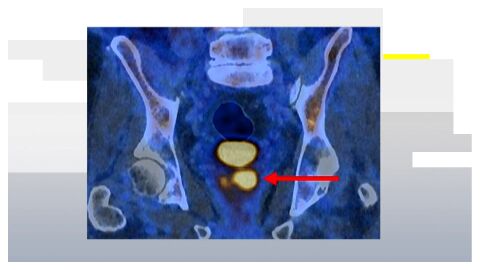

El estudio, publicado recientemente, ha demostrado por primera vez una relación directa entre la exposición a partículas diésel y la aparición de arritmias ventriculares sostenidas, una de las alteraciones cardíacas más graves, ya que con frecuencia puede derivar en fibrilación ventricular. Estas arritmias están vinculadas con el estrés oxidativo del miocardio, un proceso en el que se generan radicales libres que dañan las células del corazón y favorecen la fibrosis del tejido cardíaco.

Para estudiar posibles soluciones, los investigadores probaron nanopartículas de óxido de cerio en modelos animales expuestos a contaminación diésel. Los resultados fueron prometedores: las propiedades antioxidantes de este material redujeron de forma significativa las arritmias provocadas por la contaminación. El compuesto actúa capturando radicales libres de oxígeno, responsables del estrés oxidativo que está en el origen de numerosas enfermedades.